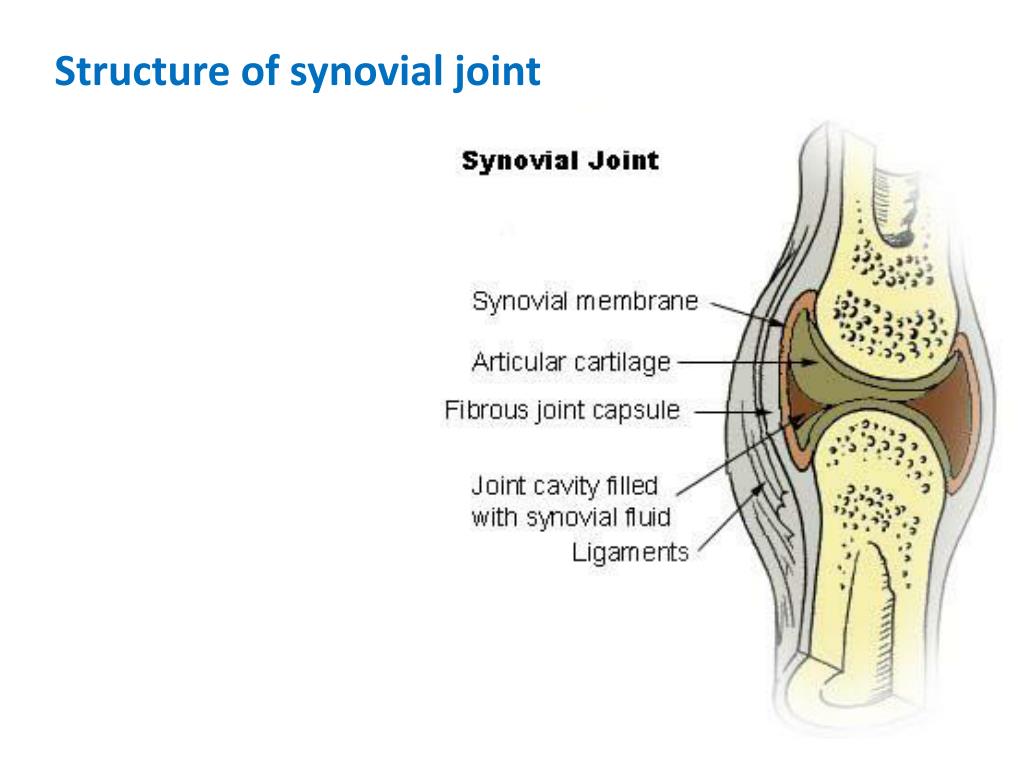

Рисунки Суставов: Анатомические Иллюстрации